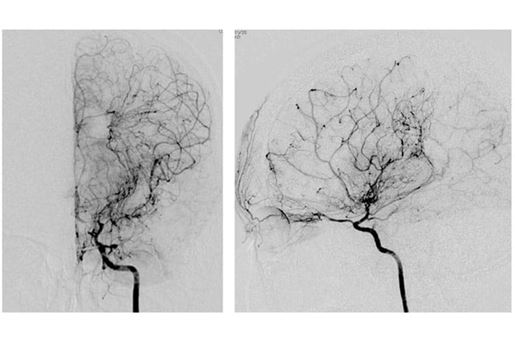

- Adult moyamoya disease and syndrome is a rare disorder characterized by an abnormal formation of abnormal network of dilated and fragile blood vessels in the brain. It is a heritable disease and carries a significant morbidity and mortality.